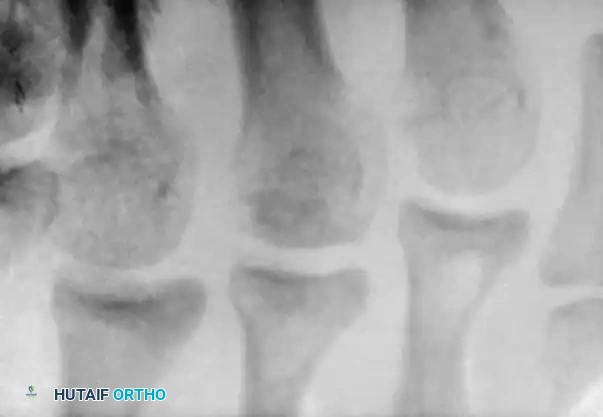

The epiphysis typically appears in girls at approximately 10 years of age and in boys at 12 years of age, with fusion occurring about 2 years later. Patients present with localized pain and tenderness over a prominent proximal fifth metatarsal, exacerbated by weight-bearing and sports. Physical examination reveals soft-tissue edema, local erythema, and pain elicited by resisted eversion or extreme plantar flexion and dorsiflexion.

Standard anteroposterior and lateral radiographs often fail to visualize the lesion adequately; an oblique view is mandatory. Hoerr et al. demonstrated that this epiphysis is visible on 99% of oblique radiographs in this age group. Imaging typically reveals enlargement, widening of the cartilaginous-osseous junction, and occasionally fragmentation of the epiphysis.

Enlargement and fragmentation of the epiphysis characteristic of Iselin disease.